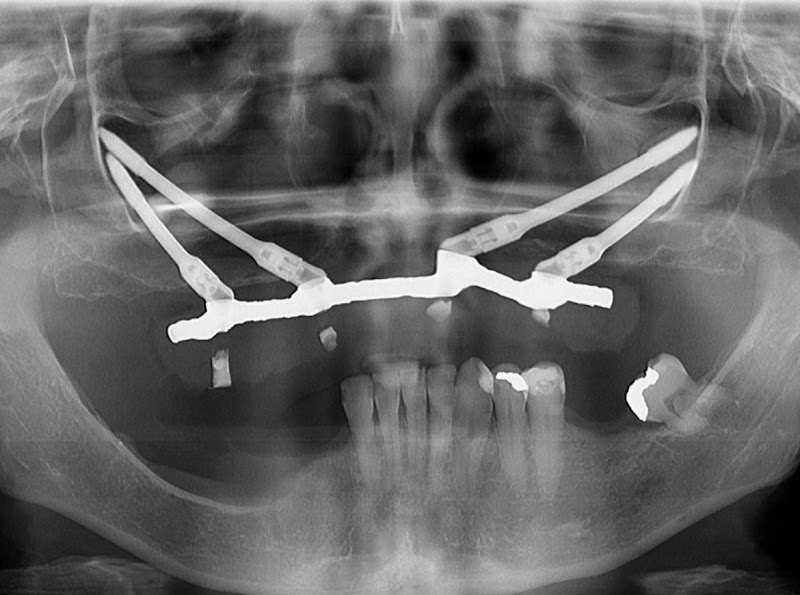

Implantes Zigomáticos - Casos extremos - reabilitação de maxilares atróficos - protocolos complexos de retratamento